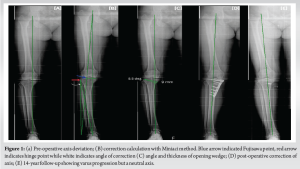

A 56-year-old female was diagnosed with medial compartment osteoarthritis (Kellgren-Lawrence grade 3) with varus malalignment (Fig. 1a) and medial meniscus posterior root tear. The patient was planned for arthroscopic medial meniscus root repair and MOW-HTO. The planned correction angle was 8.5° with opening wedge thickness of 9 mm (Fig. 1c). Meniscus root was repaired with a suture anchor. For the osteotomy, a small vertical incision was taken over the medial aspect of the proximal tibia below the joint line and midway between anterior and posteromedial margins of tibia. The pes anserinus tendon was identified and superficial medial collateral ligament (sMCL) partially released at that level. A radiolucent Hohmann retractor was strategically placed from under the released sMCL going posteromedial to protect the neurovascular structures. The Hohmann was placed obliquely all the way along the osteotomy line which was directing toward the tip of fibula under fluoroscopy guidance (Fig. 2). Osteotomy path was positioned using 2 K-wires starting just above pes anserinus level at the medial metaphyseal flare of tibia aiming toward the tip of fibula. Once sure, osteotomy was done was oscillating saw and opened using “3 chisel technique.” The correction was planned using Miniaci technique at Fujisawa point, i.e., 62% of tibial plateau as measured from medial side (Fig. 1b). Care was taken to maintain the lateral hinge. The open wedge was filled with tricalcium phosphate (TCP) bone substitute toward the cortex to prevent post-operative collapse and loss of correction. Osteotomy site was secured with locking TOMOFIX plate. Drilling for screws was done carefully not to cross far beyond the distal cortex. The TCP and the plate were purposely kept postero-medially and fixed in knee extension to maintain the posterior tibial slope angle. The procedure was uneventful. On post-operative day 1, the patient complained of decreased sensation over the posterolateral area of leg and sole of foot along with generalized tingling in the lower limb with inability to flex the great toe (Video 1a). Rest of the neurovascular examination was normal. Post-operative X-rays showed good fixation with no protruding hardware. Magnetic resonance imaging of lumbosacral spine was done which showed mild disc bulge at L4-L5 and L5-S1 with no nerve compression or canal stenosis. This could not be related to patient’s symptoms. Nerve conduction velocity (NCV) test was done at 3 weeks which showed right tibial nerve injury pattern around knee level with moderate axonotmesis (Fig. 3a). Since the nerve was in axonotmesis, a conservative trial with a close follow-up was planned for the patient. The patient was given electrical stimulation therapy, interferential current therapy, physiotherapy, and pregabalin course. On 2-month follow-up, there was no pain. The patient was mobilizing full weight bearing. However, there was no neural recovery clinically. On 4-month and 1-year follow-up, great toe flexion power was 2/5 and there was a 50% subjective improvement in sensory complaints. The X-rays showed good progressive union (Fig. 4). Unfortunately, after this, the patient was lost to follow-up and came back to us after 5 years (6-year post-surgery). The patient had the osteotomy plate removed at another hospital. At this time, the patient had persistent paresthesia (subjectively around 40%) and great toe flexion was 4/5. The last follow-up is 14-year post-surgery where the motor function has recovered completely with some residual paresthesia (Video 1b).

However, the patient complained of discomfort after walking for long distances. The NCV at this stage was suggestive of chronic tibial nerve injury (Fig. 3b). Long leg X-ray showed some loss of correction with axis passing through 50% point (Fig. 1e), but the patient had no arthritis-related complaints.